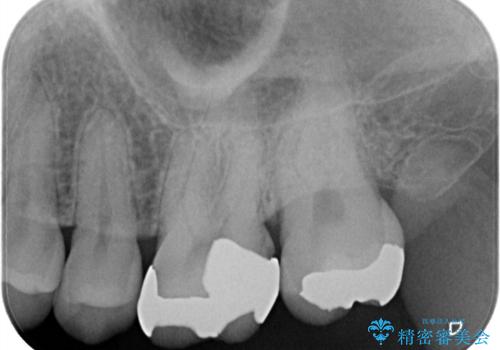

銀の詰め物が外れた。プラチナゴールドインレー

- 銀の詰め物が外れたことを主訴に来院されました。

適合の良い修復を希望されましたので、プラチナゴールドインレーにて治療を行っております。

PGA(プラチナゴールド)インレーは適合もよく、壊れるリスクも極めて少ない修復です。